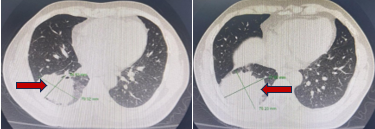

Cắt lớp vi tính lồng ngực (5/4/2019):

Hình 3:  Hình ảnh khối u thuỳ dưới Phổi phải, kích thước 70×75 mm (mũi tên đỏ) nhiều tổn thương thứ phát 2 phổi, hạch trung thất và rốn phổi phải (mũi tên vàng)